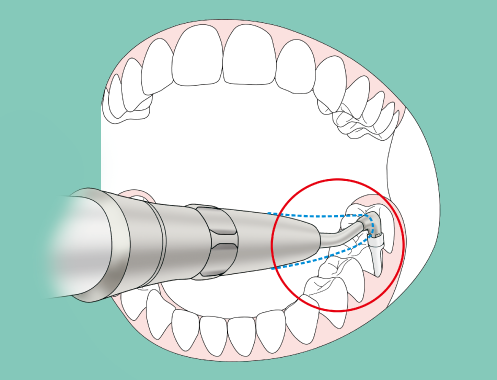

La fina punta de boquilla presenta el grado de flexibilidad justo para pasar suavemente sobre la superficie de la pieza e insertarse con facilidad en las estrechas bolsas así como en las superficies de la raíz de las piezas adyacentes, al tiempo que vela por la comodidad del paciente.

La forma alargada y estrecha de la boquilla está concebida para acceder con facilidad a las zonas que exijan insertar la pieza de mano con un determinado ángulo como, por ejemplo, entre los molares.